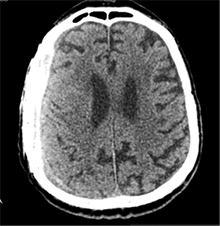

Praėjus dar 2 sav., pacientas iš slaugos ligoninės atvežtas dėl vangumo, dezorientacijos, nerišlios ir sulėtėjusios kalbos. Atlikus GKT, dešinėje pusėje po kraniotomijos lopu įtarta poūmė (ūmi) epidurinė hematoma, nesant VSD. Per parą pacientas operuotas. Operacijos metu po minkštaisiais audiniais rasta kraujo sankaupa su seroziniu komponentu, paimtas bakteriologinis pasėlis. Po KPL rasta krešulių su skystu krauju ir seroziniu komponentu. Paimtas antras bakteriologinis pasėlis, įtariant infekciją. Hematoma (seroma) pašalinta. Žaizda plauta mažos koncentracijos betadinu ir fiziologiniu tirpalu. Kraujavimo iš KSD nepastebėta. Nuspręsta KPL grąžinti – labiau tikėtina epidurinės seromos (EDS) diagnozė. Siekta uždaryti „negyvąjį“ epidurinį tarpą, pakabinant KSD centre prie KPL siūlais, tačiau KSD buvo nepaslankus, tampriai priaugęs prie smegenų. Atlikus kontrolinę GKT (9 pav.), nustatyta teigiamų pooperacinių pakitimų, smarkiai sustorėjęs KSD, tarpas tarp KPL ir KSD. VSD nenustatyta. Po operacijos paciento bendroji būklė buvo stabili. Reakcija buvo kiek sulėtėjusi, tačiau vyras gebėjo atsakyti į elementarius klausimus. Teigiama klinikinė dinamika. Po savaitės pacientas tapo labai vangus, sulėtėjo, skundėsi silpnumu, kalbėjo nesklandžiai. Pakartojus GKT (10 pav.), nustatyta padidėjusi epidurinė skysčio sankaupa, panaši į mišraus tankio hematomą (apie 64 ml tūrio) dešinėje pusėje frontotemporoparietaliai, padidėjusi VSD į kairę – iki 4 mm. Kadangi pacientas per tą patį randą jau operuotas 6 kartus, o po operacijų pastebimos vis atsinaujinančios pakartotinės EDS, priimtas sprendimas neskirti operacinio gydymo. KPL turėjo daugybinių perforacijų, todėl nuspręsta atlikti subgalinio tarpo punkciją, tikintis, kad per perforacijas išbėgs EDS. Atlikus punkciją, gauta 20 ml serohemoraginio skysčio. Po procedūros paciento būklė pagerėjo, jis tapo kiek aktyvesnis, tačiau efektas nebuvo patenkinamas. Kitą dieną nuspręsta punktuoti pakartotinai, gauta 4 ml serohemoraginio skysčio. Tūris buvo nepakankamas teigiamam efektui gauti. Priimtas sprendimas skirti lašinių infuzijų ir švelnią osmoterapiją neurologinei simptomatikai sumažinti. Punkcijos nedavė norimo efekto, todėl nuspręsta suformuoti poodinę neigiamo slėgio drenažinę sistemą po minkštųjų audinių lopu. Į subgalinį tarpą įvestas 20G periferinės venos kateteris, fiksuotas prie odos ir sujungtas su uždara vakuumine sistema, tikintis nuolatinio drenavimosi smegenų kompresijai sumažinti. Per 5 lovadienius išsiskyrė apie 50 ml serohemoraginio skysčio. Atlikus kontrolinę GKT, buvo matyti teigiama dinamika (11 pav.). Dėl infekcijos profilaktikos vakuuminė sistema pakeista 2 kartus. Įvedus vakuuminę sistemą, po 12 lovadienių paciento būklė pagerėjo, jis tapo aktyvesnis, į klausimus atsakydavo prasmingai, paliepimus vykdydavo visomis galūnėmis. Vakuuminė sistema pašalinta. Po 2 dienų atlikta GKT (12 pav.). EDS dešinėje pusėje regresavo, smegenų kompresijos nenustatyta. Esant stabiliai būklei ir teigiamai dinamikai, pacientas grąžintas į slaugos ligoninę.

11 pav. Implantavus vakuuminę sistemą su PVK (dešinė F-T-P EDS dinamikoje sumažėjusi; išlieka nežymi VSD)

12 pav. Dešinė F-T-P EDS dinamikoje sumažėjusi (VSD nematyti)